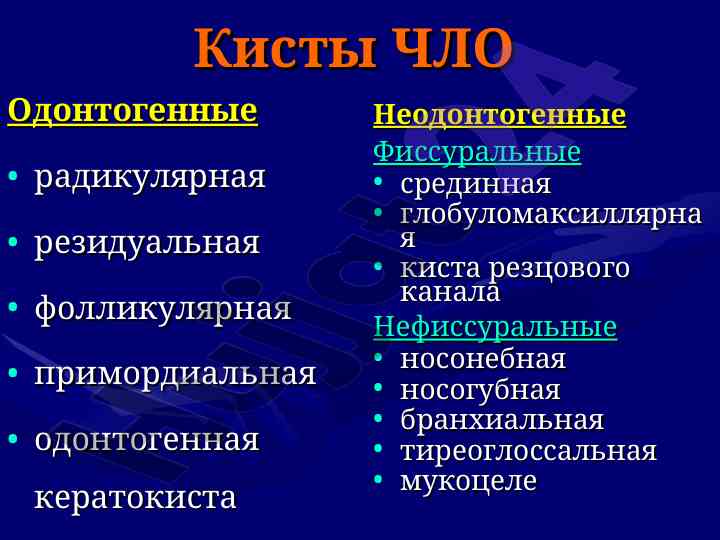

Данная лекция охватывает диагностические критерии, локализацию и структуру кист и опухолей челюстно-лицевой области, включая одонтогенные и неодонтогенные кисты.